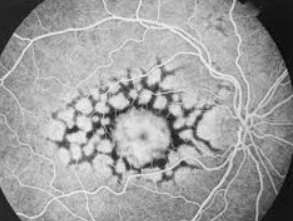

Tests that may be used include: visual fields; visual acuity; ophthalmoscopy; slit lamp examination; fluorescein angiography; and fundus photography.